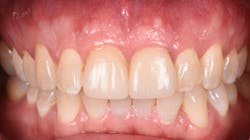

Figure 12: Pre-op clinical photo shows the discrepancies and disharmony of the gingival height. Incisions for esthetic crown lengthening on tooth No. 9 were done via the Er:YAG laser in contact mode (20 pps/60 mJ) to remove excess soft tissue in accordance with the pre-op probing depth measurements.

Figure 14: After osseous shaping and recontouring was done using the Er:YAG laser in contact mode (20 pps/80 mJ). All bony ledges and crestal bone were removed on teeth Nos. 9–11.

Figure 15: Immediate post-op of tissues repositioned into place. Simple interrupted sutures were used.

Figure 16: Two-year post-op shows gingival health and maintenance of gingival tissues.

The Er:YAG laser has been more recently known for its ability to remove calculus from a titanium implant surface as well as detoxification (figures 17–21).9 Many authors have shown the laser’s use in combination with mechanical debridement to be superior when using a regenerative approach to treat peri-implant diseases (figures 22–26).10 A particular feature of this laser is the microexplosions that occur when the laser energy is absorbed by water. The volume of these explosions suddenly expand up to 1,000 times, covering more surface area of a titanium implant. It has been found that both contaminated debris and the contaminated oxide layer are removed as a result of these microexplosions.11